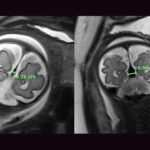

After med-flighting a newborn from Miami to Boston for urgent treatment, MRI obtained at Boston Children’s showed diffuse bihemispheric brain injuries (red arrows), new since the initial MRI (green arrows showing normal brain tissue).

Whole-body edema (anasarca) on the MRI (blue arrows) is secondary to overwhelming heart failure.

Likely no post-natal intervention, even on day one, would have circumvented this rapid evolution.